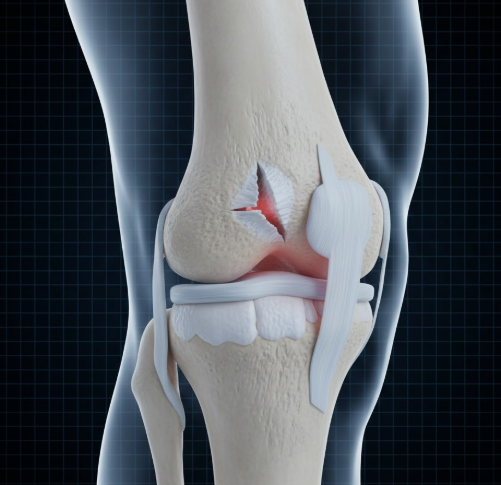

- 전방 십자인대 파열

- 축구, 농구, 스키처럼 갑작스러운 방향 전환과 점프 착지가 많은 운동에서 발생

- 무릎이 ‘뚝’ 하고 꺾이는 느낌과 함께 극심한 통증 발생

- 무릎이 빠르게 부어오르고 불안정해짐

- 반월상연골의 역할

- 무릎 안쪽과 바깥쪽에 위치한 초승달 모양의 연골

- 충격을 흡수하고 무릎 관절을 안정시키는 역할 수행

- 반월상연골 파열 원인

- 급격한 회전 동작

- 쪼그려 앉았다 일어나는 동작

- 노화로 인한 퇴행성 변화로도 발생 가능

- 잠김 증상

- 찢어진 연골 조각이 관절 사이에 끼면서 발생

- 무릎이 갑자기 펴지지 않거나 움직임이 제한됨